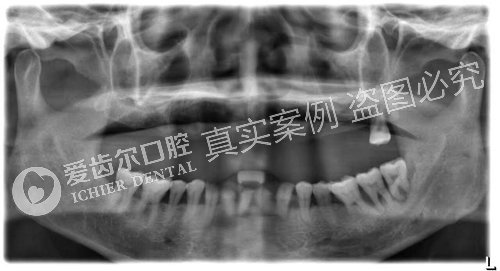

术前牙片,检测口腔或牙槽骨基本情况

拍片检查种植体情况,种植体与骨组织间紧密贴合,无松动、无炎症等不良情况

术后牙片,种植体与牙组织密合